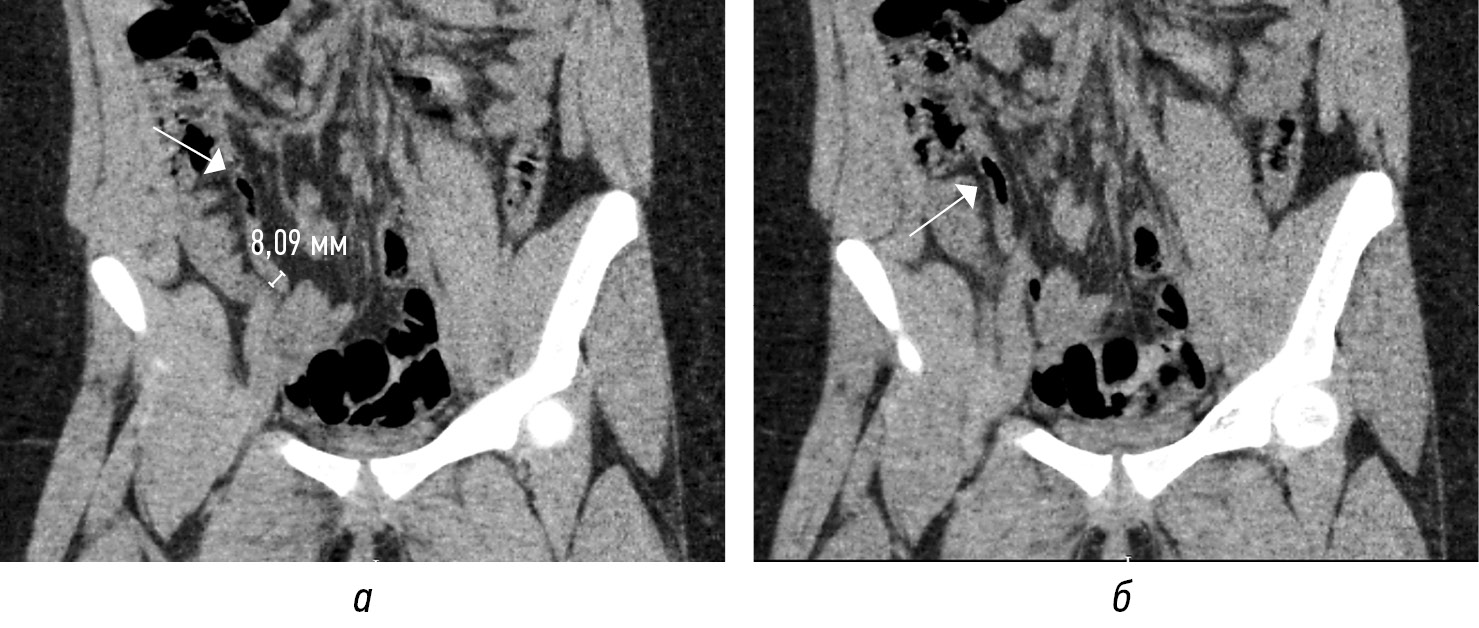

Просвет аппендикса может расширяться за счет неоднородного внутреннего содержимого без наличия (рис. 6, а, г) или с присутствием (рис. 6, б, в, д, е) аппендиколита. Другие косвенные признаки ОА: отек периаппендикулярной жировой клетчатки (рис. 7, а, б; 8, а, б); утолщение за счет отека прилежащей стенки кишки (рис. 9, а–г); расширение просвета кишки за счет газа иди жидкости с ослабленной перистальтикой; периаппендикулярное жидкостное скопление или абсцесс (рис. 10, а, б); лимфоаденопатия (рис. 11, а); абдоминальный выпот (рис. 11, г) [3, 16, 18].

Рис. 7. КТ-изображения во фронтальной (а) и в сагиттальной (б) плоскостях в нативную фазу: вокруг аппендикулярного отростка (стрелки) тяжистое уплотнение жировой клетчатки. Купол слепой кишки (пунктирная стрелка)

Fig. 7. CT images in the frontal (a) and sagittal (b) planes in the native phase: around the appendicular process (arrows) there is a heavy thickening of adipose tissue. Dome of the cecum (dotted arrow)